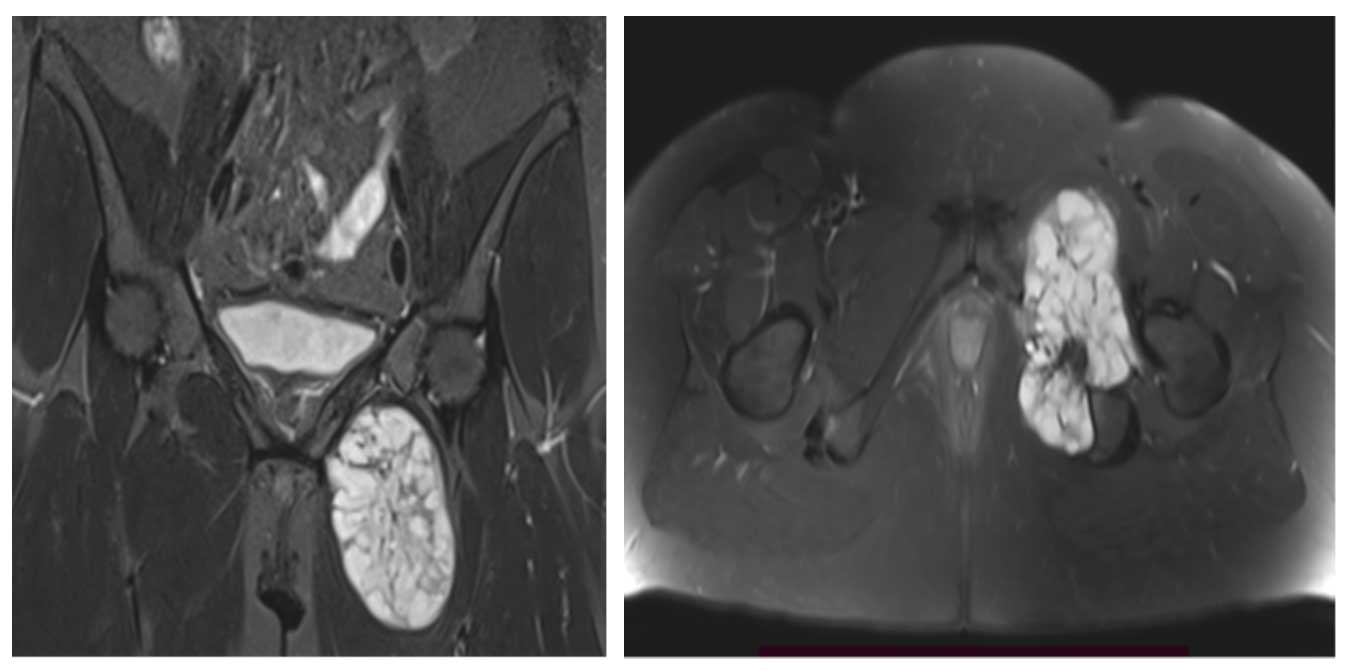

Ameliyat Öncesi: MR’da aynı lokalizasyonda kemikte harabiyete neden olmuş büyükçe tümör dokusu görülmekte.